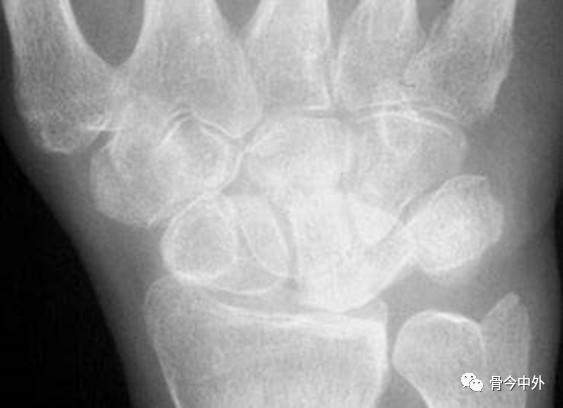

图37

1.月骨-三角骨间隙平行关系缺失致掌骨弧线Iand II中断。

2.月骨和舟骨平行,而与其他腕骨不平行。

3.舟骨缩短提示向掌侧倾斜。

4.月骨平行于舟骨,其三角形状提示为掌侧倾斜所致。

5.近排腕骨不是一个整体,因为弧线I中断。

图38 侧位显示月骨向掌侧倾斜

最后诊断:掌屈不稳伴月骨-三角骨关节脱位。